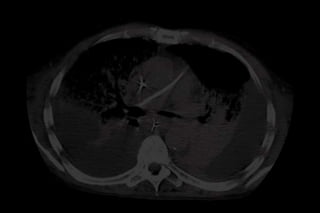

ANESTESIA E ATELECTASIA

Áreas não dependentes

FIO2 100 %

Áreas dependentes

ANESTESIA E ATELECTASIA Altasconcentrações de O2 causam atelectasias de absorção 5 min após recrutamento. FIO2 40% retarda colapso alveolar. Rohen, HU. Anesthesiology, 1995

ANESTESIA E ATELECTASIA Áreas não dependentes FIO2 100 % Áreas dependentes